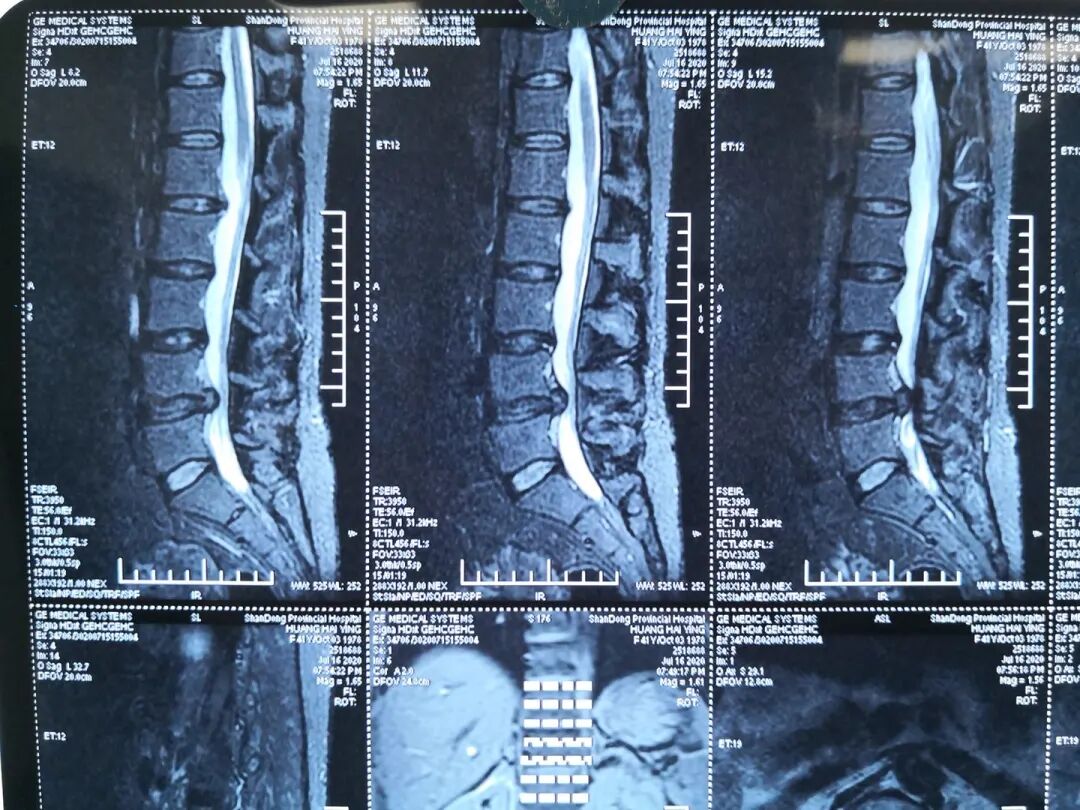

患者,黄某某,女,41岁,因左下肢疼痛伴麻木2年,加重半年入院;患者2年前无明显诱因出现左下肢疼痛,疼痛自臀部放射到小腿外侧,伴有足背部麻木感,活动后加重,于当地医院行CT检查示L4/5腰椎间盘突出,患者未予特殊治疗,近半年以来,感左下肢麻木疼痛加重,症状反复发作,行走后加重,影响日常生活,于院外的保守治疗无效。

查体: 腰椎生理曲度存在,腰椎屈伸活动稍受限,L4/5棘突间及 棘突旁压痛,伴左下肢放射痛,左侧足背部感觉减退,双下肢肌力正常,左路背伸肌力4级一,左下肢直腿抬高试验及加强试验阳性,双侧膝腿反射(+),双侧跟健反射(+),巴氏征(-),双下肢水梢毛细血管充盈良好。

图1:术前磁共振

图2:术前磁共振